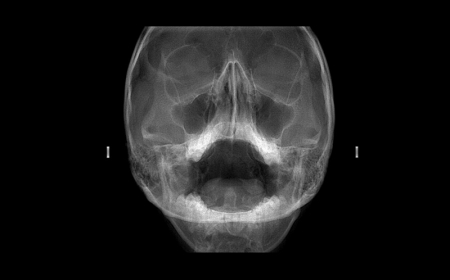

Seios da Face

exame seios da face na neox radiologia digital odontologica odontologia uberaba

• Towne

• Waters